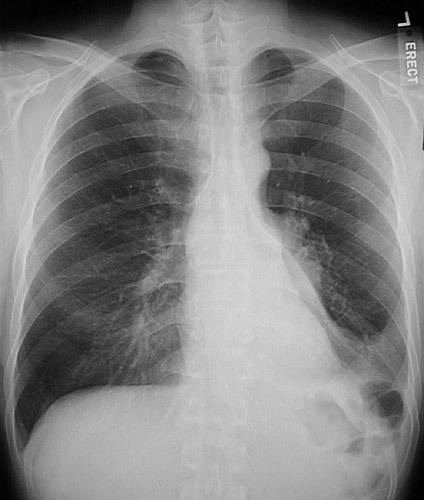

This PA chest radiograph reveals atelectasis of the left lower lobe to the left of the heart border. The mediastinum and heart are shifted slightly to the left. There was a squamous cell carcinoma at the hilum.